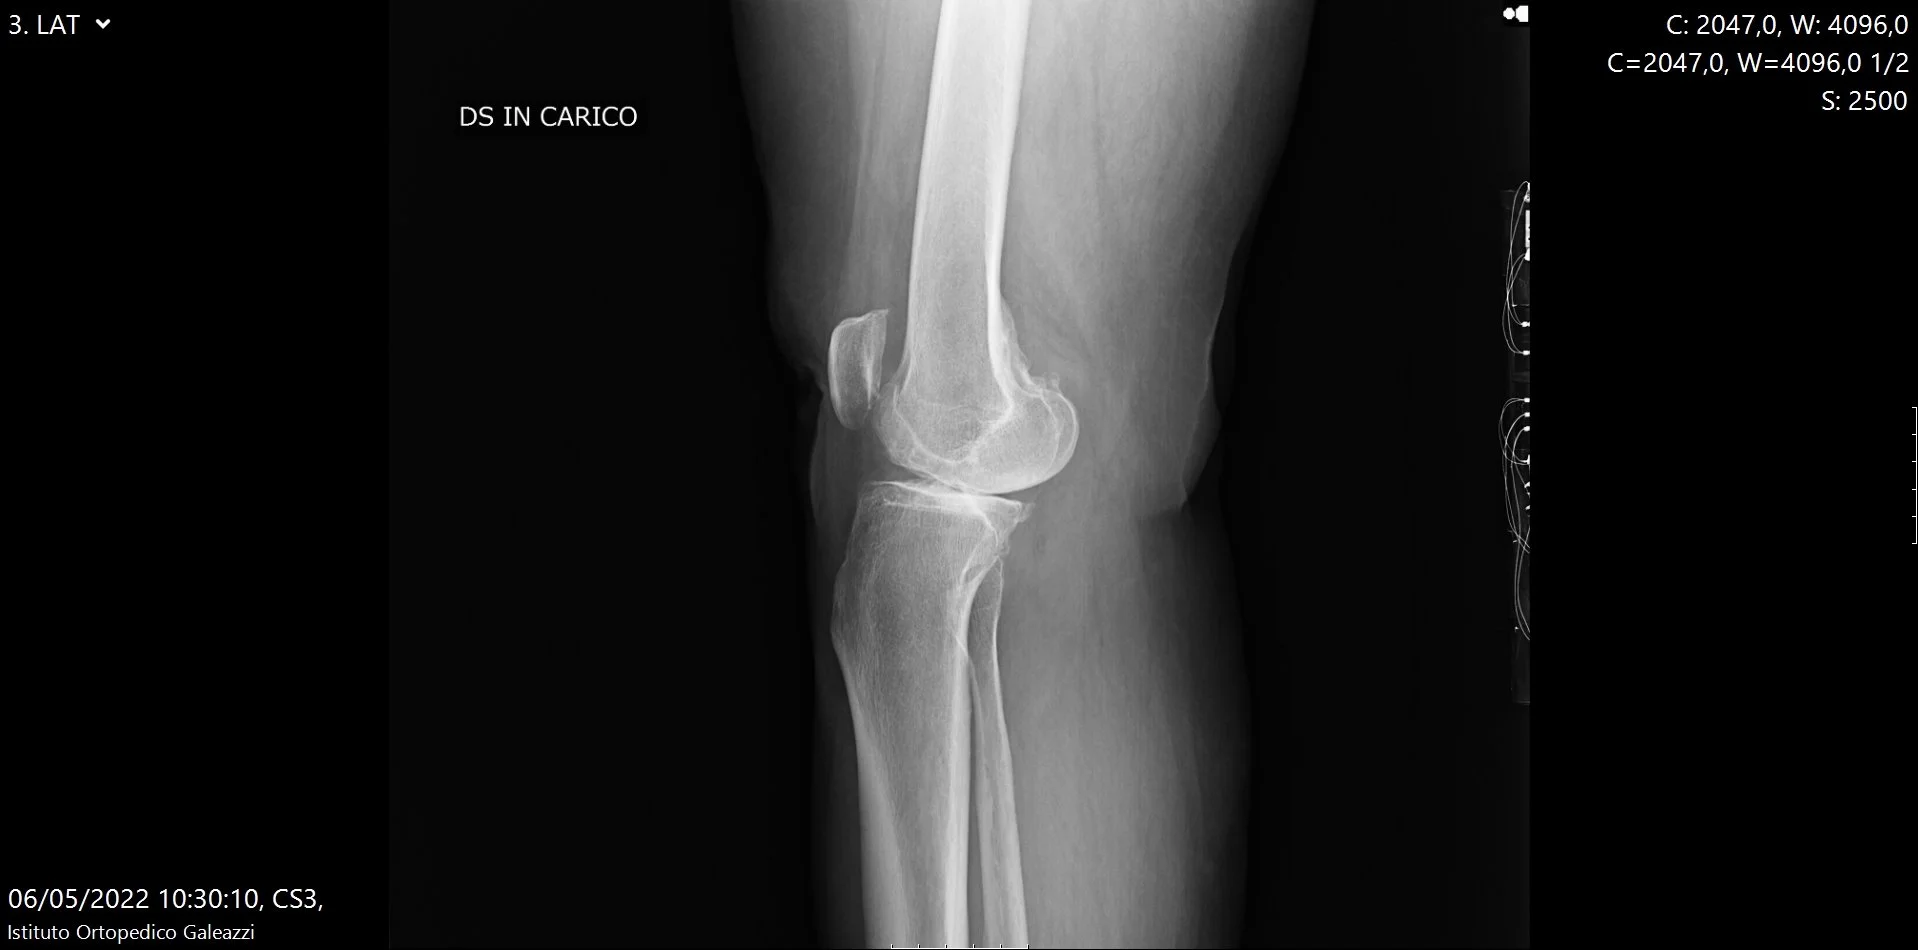

La proiezione laterale completa lo studio radiografico standard e permette di analizzare il ginocchio su un piano diverso rispetto alla proiezione antero-posteriore.

È utile per valutare:

• il profilo articolare

• le componenti posteriori dell’articolazione

• eventuali alterazioni ossee o segni indiretti di sofferenza articolare

Pur non essendo la proiezione principale per la valutazione dello spazio articolare, la radiografia laterale fornisce informazioni complementari importanti e contribuisce a una lettura completa e corretta del ginocchio.

Radiografia laterale del ginocchio sotto carico per valutazione dell’artrosi